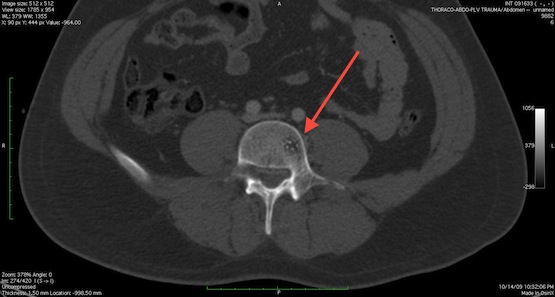

Злокачественные новообразования

Раковые опухоли – наиболее опасная причина появления шишек и наростов на позвоночнике. Они могут быть первичными, то есть возникают непосредственно из позвоночника, или вторичными – их причиной является метастазирование злокачественных процессов, локализующихся в других органах. Рак позвоночника представляет собой редкое заболевание, но исключать его также не стоит – это крайне опасная болезнь, которая часто ведет к смерти больного.

Метастазы в позвоночник

В число наиболее распространенных злокачественных новообразований позвоночного столба входят:

- хондросаркома, которая образуется из хрящевых тканей;

- остеоритарная саркома разрастается непосредственно в позвонках;

- миелома поражает нервные клетки и разрушает тела позвонков, опухоли бывают одиночными и множественными;

- хондрома – злокачественная опухоль, произрастающая из хорды, характерна для больных среднего и преклонного возраста;

- саркома Юинга диагностируется в детском возрасте и поражает структуры спинного мозга.

Если речь идет о вторичных опухолях, то чаще всего метастазы в костные ткани дают злокачественные заболевания молочных желез, простаты, почек, щитовидной железы и респираторных органов. Пропальпировать новообразование на позвоночном столбе при раке можно только в том случае, если оно растет в переднем направлении – в иных случаях его можно обнаружить только при диагностике или на поздних стадиях, когда опухоль достигла достаточно больших размеров. Ранние этапы раковых болезней зачастую протекают бессимптомно, поэтому их обнаруживают достаточно поздно.